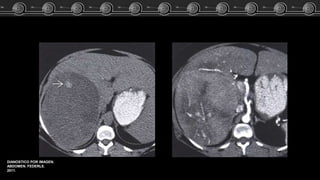

Fem de 83 años…. El estudio TC demostró lesión focal a nivel del lóbulo

izquierdo del higado.

ARCHIVO DOCENTE DE

TOMOGRAFÍA Y

RESONANCIA C.M.C.

Adenoma, Hemangioma ó HNF?? Caso Clínico